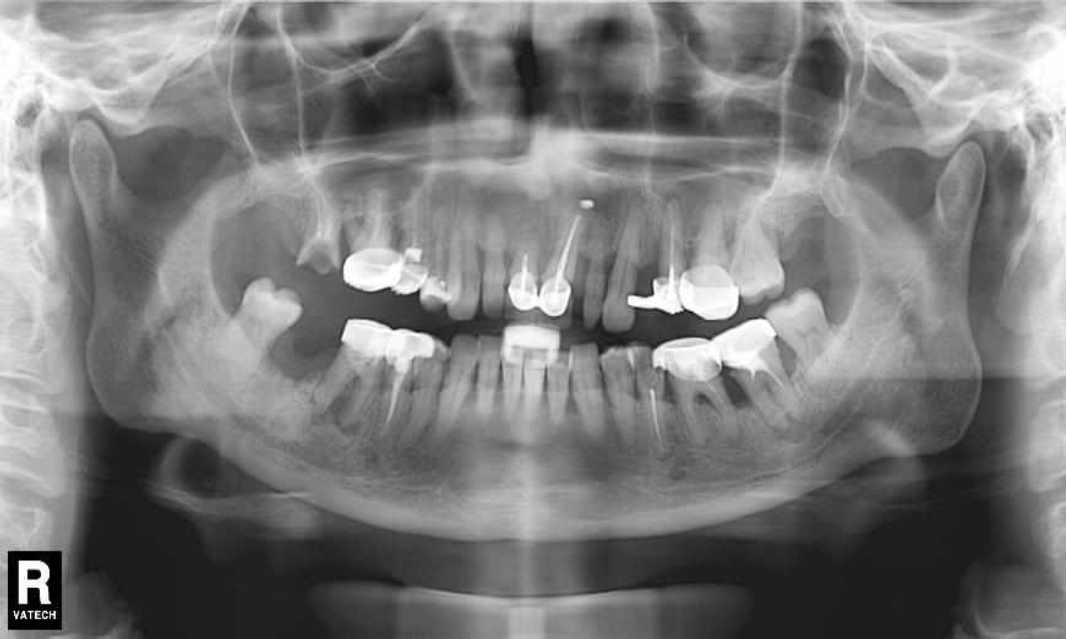

Ранее у пародонтолога не наблюдалась. При осмотре выявлены: неудовлетворительная индивидуальная гигиена полости рта, пародонтальные карманы до 7 мм, обильная кровоточивость и гноетечение из пародонтальных карманов, подвижность зубов 4.2, 4.1, 3.1, 3.2 II степени, обильные над- и поддесневые зубные отложения (рис. 1). На ортопантомограме отмечается резорбция костной ткани до ½ длины корня, очаги остеопороза (рис. 2). Пациенту был поставлен диагноз хронический генерализованный пародонтит тяжелой степени тяжести. При осмотре была составлена пародонтограмма с использованием компьютерного зондирования (рис. 3).

Рис. 2. Ортопантомограмма исходной ситуации пациента состояния полости рта